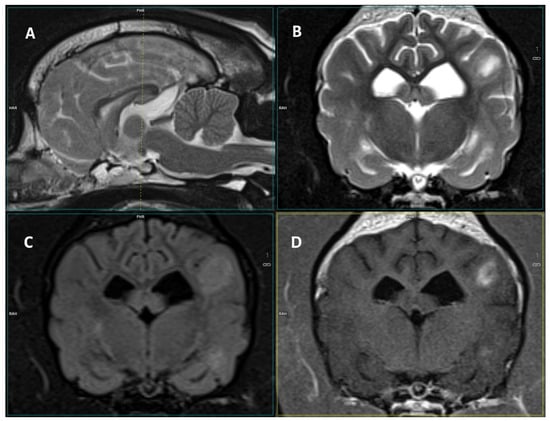

Figure 2.

Images of a 3-T MRI study of a 5-year-old male French Bulldog. (A) Mid-sagittal T2-W, (B) T2-W transverse, (C) FLAIR, (D) T1 post-contrast transverse images of the brain. At the level of the caudal margin of the interthalamic adhesion, in the left parietal and temporal regions, there are diffuse T2-W and FLAIR hyperintense lesions with cloudy margins. They display clear, inhomogeneous contrast enhancement. In addition, partial obliteration of the sulci is observed in correspondence to the lesions.

The lesions were mostly T2-W hyperintense, FLAIR/STIR hyperintense, and T1-W isointense, showing contrast enhancement (Table 3, Figure 1 and Figure 2). A total of 44.4% (n = 12) of dogs displayed meningeal contrast enhancement.